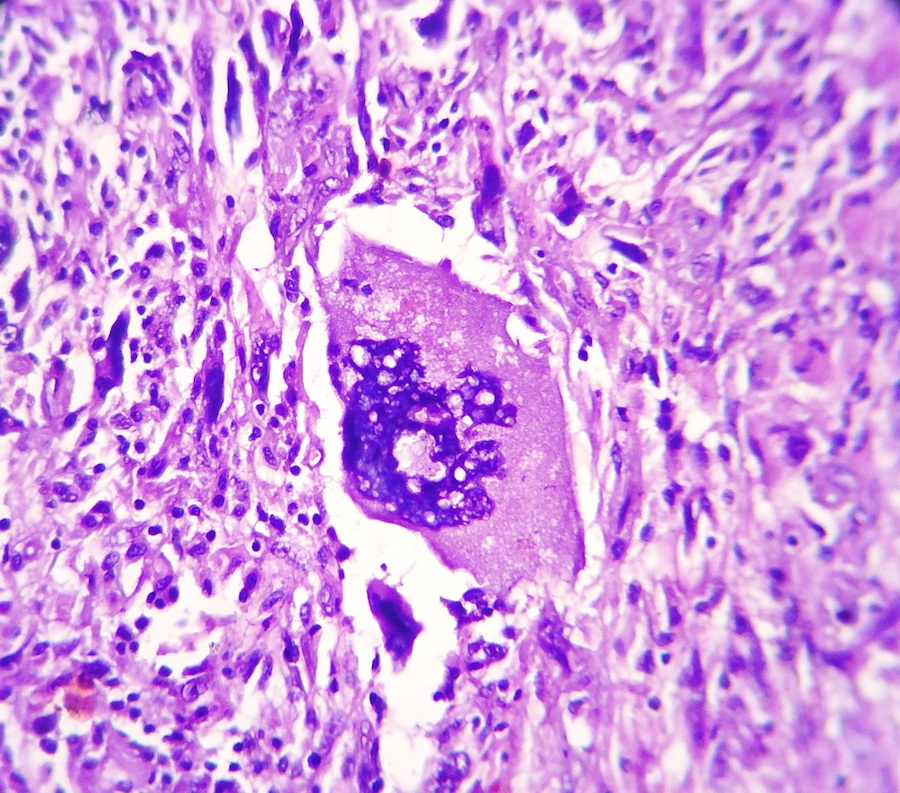

Микрофотографии гистологии глиобластомы головного мозга